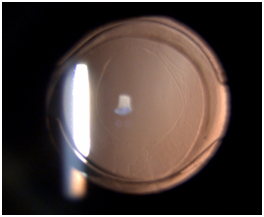

Intraoperative challenges in paediatric cataract surgery are running off capsulorhexis due to elasticity of the capsule, positive intravitreal pressure, intraoperative miosis and wound leak. These complications have significantly reduced using closed chamber surgical technique. Postoperative complications include uveitis, posterior capsule opacification, glaucoma, pupillary capture and retinal detachment. Visual axis opacification (VAO) is the most common complication after a successful cataract surgery in children. The PCO is amblyogenic and the purpose of surgery is defeated if long-term clear visual axis is not achieved. A child’s eye tends to show more tissue reaction than an adult. The inflammatory response can be managed with the use of intensive topical steroid tapered over a period of 6 to 8 weeks. Topical antibiotics are instilled for two weeks and cycloplegic eye drops for four weeks to prevent posterior synechiae formation. Refraction should be done as soon as inflammation subsides and appropriate correction with aphakic glasses, contact lenses or bifocals should be provided based on the age of the child (Figures 1–5).

Figure 1 Lamellar cataract.